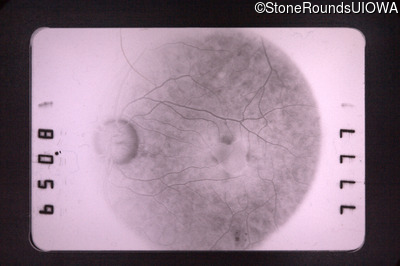

Fluorescein Angiography - Right - 20/50 +1

Exemplar